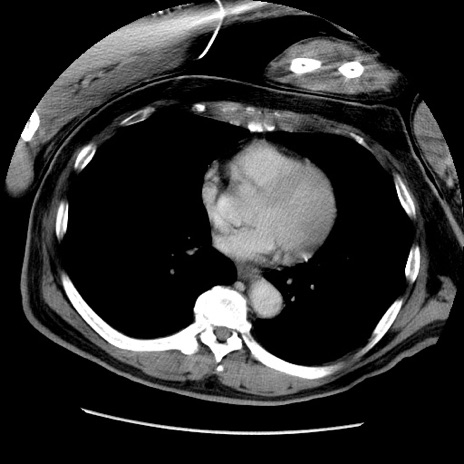

症例22(横断像)

【症例】50歳代男性

【主訴】腹痛

【現病歴】AVMからの被殻出血のため回復期リハ病棟入院中。 本日午後3時頃急に下腹部痛が出現した。

【既往歴】AVM、被殻出血、虫垂炎、高血圧

【身体所見】意識晴明、左半身不全麻痺、会話の理解は良好、36.5°C、腹部:膨隆、全体に板状硬、下腹部正中に圧痛点あり、反跳痛-、筋性防御不明、右下腹部にope scar

【データ】WBC 9400、CRP 0.06